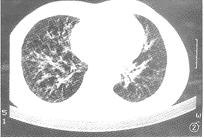

影像學檢查X線攝片檢查對診斷髖關節結核十分重要,必須兩髖關節同時攝片以資比較,早期病變只有局限性骨質疏鬆,質量好的X線片可顯示出腫脹的關節囊,進行性關節間隙變窄與邊緣性骨破壞病灶為早期X線徵象,隨著破壞的加劇,出現空洞和死骨,嚴重者股骨頭部幾乎消失。後期有病理性脫位,經治療後骨輪廓邊緣轉為清晰時提示病變趨於靜止。

CT與MRI檢查可獲得早期診斷。能清楚顯示髖關節內積液多少,能揭示普通X線片不能顯示的微小骨骼破壞病灶。MRI還能顯示骨內的炎性浸潤。診斷與鑑別診斷根據病史、症狀與影響學表現,診斷不難,須與下列疾病作鑑別診斷: